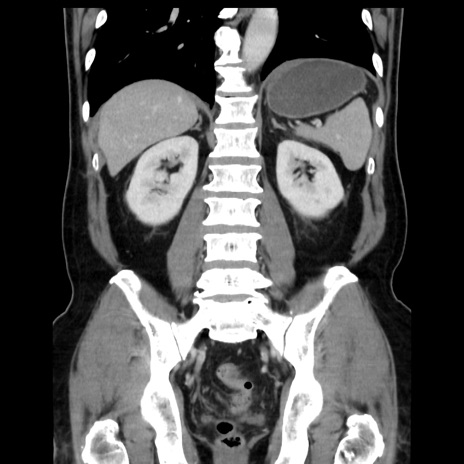

症例16(冠状断像)

【症例】 70歳代男性

【主訴】 腹痛、嘔吐

【現病歴】 約1ヶ月前より間欠的に腹痛と嘔吐あり、当院消化器内科を受診したところCTで多発する肝臓のLDAを指摘され、精査中であった。以降は消化器症状は安定していたが、2日前より嘔気と腹痛があり、同日より排便・排ガスが消失した。改善認めず、 本日、救急外来を受診した。

【既往歴】 大腸ポリープ切除後。

【身体所見】意識清明・会話良好、BT 36.3℃、BP 127/80mmHg、 P 80bpm、腹部:膨満あり、平坦・軟、上腹部正中および下腹部正中に圧痛あり、反跳痛なし、筋性防御なし。

【データ】WBC 7200、CRP 0.77